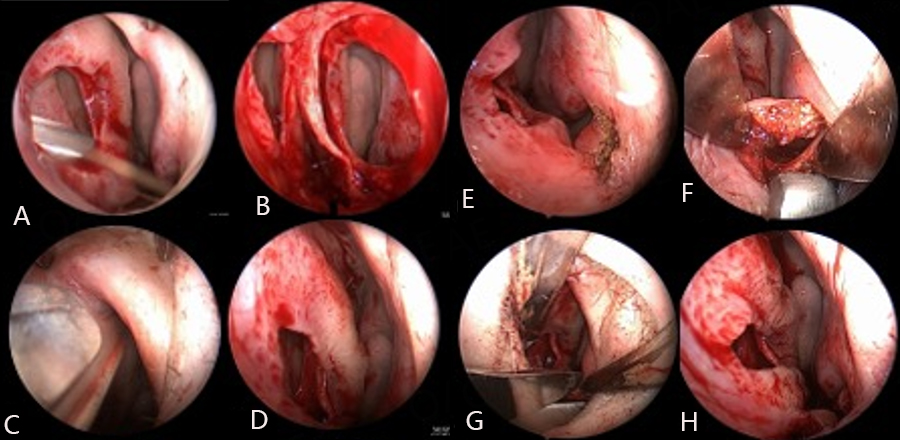

Perforation repair basic technique: Perforation length, height, and distance from the anterior perforation margin to the nasal valve angle and columella are recorded. The fundamental steps in our bilateral flap and graft repair are illustrated in Figure 1. Endoscopic photos of the left side closure are presented in Figure 2. Perforation repair is performed through a right hemitransfixion incision[13]. Mucoperichondrial/periosteal elevation proceeds on the left side through the incised circumference of the perforation margin and then superiorly towards the junction of the upper lateral cartilage (ULC) and septum. Mucosal elevation then proceeds inferiorly and laterally onto the nasal floor as determined by perforation size and position. For larger perforations, the elevation proceeds 2 cm posterior to the posterior margin. Mucosal elevation is then performed on the right side, extending through the perforation and then inferiorly and laterally onto the nasal floor. Elevation superior to the perforation’s superior margin on the right side is avoided. Flap development is first performed on the left side to accomplish complete and tension-free defect coverage. A superior bipedicled advancement flap is developed and, if necessary, an inferior bipedicled flap. The superior flap incision may start anterior to the internal valve angle as determined by perforation size and position. The incision arcs above the perforation and then for 2 cm beyond the posterior margin for larger defects to allow for flap release and advancement. Mucosa from the undersurface of the ULC can be incorporated into this flap through an intercartilaginous incision for larger perforations. The incision for the left inferior flap is made with cautery anterior and inferior to the head of the inferior turbinate. Submucosal elevation proceeds over the piriform aperture to connect to the prior elevation of nasal floor mucosa. The mucosal flap incision is made with a scissors or monopolar cautery, starting laterally at the nasal floor-inferior meatus junction and ending posteriorly at the septum-floor of nose junction 2 cm posterior to the perforation. Anteriorly, sharp undermining dissection through the hemitransfixion incision disrupts the fibrous elements binding mucosa to the nasal spine and premaxilla to allow for flap release and advancement. Superior and inferior flaps are advanced and the collapsed mucosal margins sutured with interrupted 4-0 chromic sutures on a Castroviejo needle holder with a P-3 needle slightly bent to tighten the rotation arc. Suturing of the superior margin of the superior flap to the defect’s superior cartilage margin is performed for flap stabilization when the overlap is tenuous. Attention is then directed back to the right side. A bipedicled advancement flap comprised of mucosa inferior to the perforation and adjacent nasal floor is developed. The hemitransfixion incision is extended posterolaterally onto the nasal floor and then medially to the floor-septum junction posterior to the perforation. This inferior flap is advanced superiorly over the defect to oppose the left suture line closure and support of the interposition graft. A superior flap is not developed for advancement on the right side to avoid bilateral compromise of superior septal cartilage vascularity and the risk of re-perforation. Septal deformities are addressed next, followed by the application of an autologous tissue (temporalis fascia, septal cartilage/bone, or auricular perichondrium) interposition graft. The repair is covered with thin 0.02 in soft polymeric silicone sheeting secured with a single nylon suture placed anteriorly and bolstered with folded pads of Telfa gauze. The packs are removed on postoperative day 2 and the sheeting in 10-14 days [Figure 3]. Frequent saline spray moisturization and ointment lubrication are recommended for 6 weeks post pack removal, and then as indicated for persistent dryness or crusting.

Figure 2. Endoscopic photos of left-side mucosal flap closure. (A) Perforation margin rimmed with #15 blade; (B) Bilateral mucosal flap elevation; (C) Superior incision may extend anteriorly through valve angle; (D) Superior flap advanced inferiorly; (E) Anterior cautery incision for inferior flap; (F) Elevation connecting incision over piriform aperture to previously elevated nasal floor mucosa; (G) Inferior flap incision made with scissors; (H) Flaps advanced to collapse perforation margin for tension-free suture closure; Flaps span (bridge) over the underlying defect’s cartilage margin.